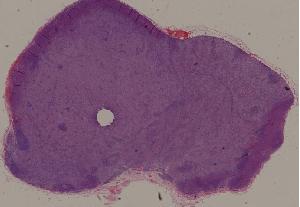

77. Chronic pyelonephritis